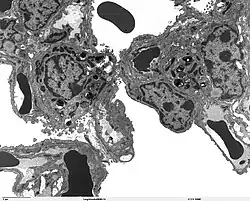

SP-A1 is primarily synthesised in type II alveolar cells in the lung, as part of a complex of lipids and proteins known as pulmonary surfactant. The function of this complex is to reduce surface tension in the alveoli and prevent their collapse during expiration. The protein component of surfactant helps in the modulation of the innate immune response, and inflammatory processes.

Alveolar sac region of the lung - TEM

SP-A1 is a member of a subfamily of C-type lectins called collectins. Together with SP-A2, they are the most abundant proteins of pulmonary surfactant. SP-A1 binds to the carbohydrates found in the surface of several microorganisms and helps in the defense against respiratory pathogens.[7][8][9]